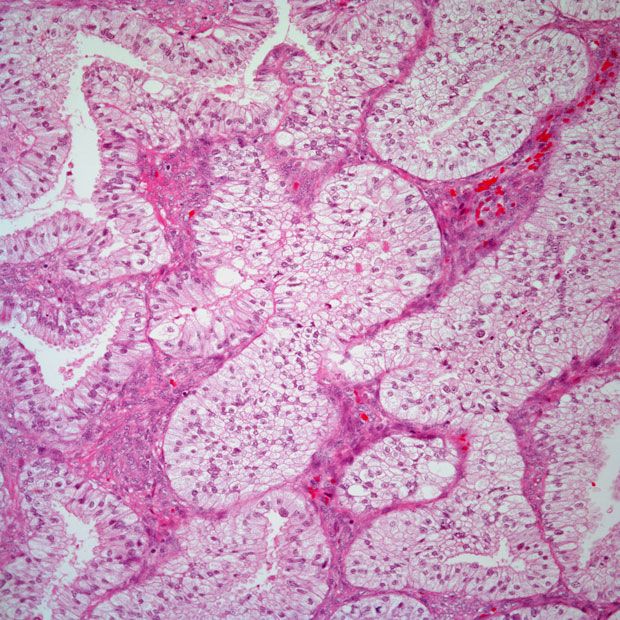

Фотографии опухоли медуллярной аденокарциномы